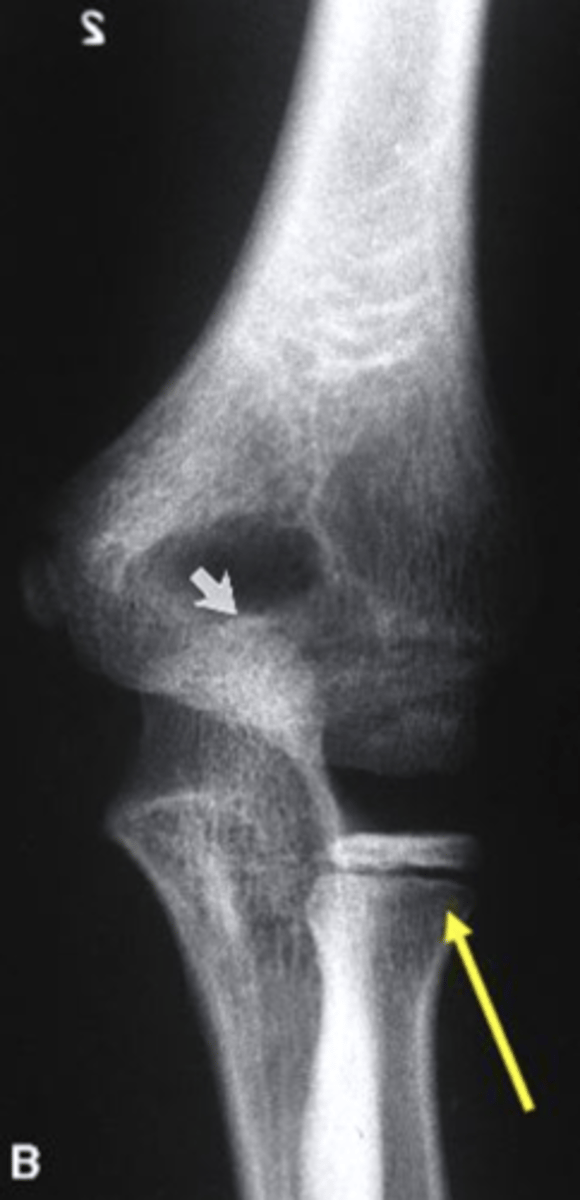

What is highlighted by the yellow arrow in the image of the elbow?

growth plate of the radius